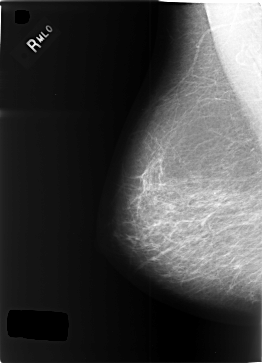

C_0345_1.RIGHT_MLO

RIGHT_CC LINES 5752 PIXELS_PER_LINE 4184 BITS_PER_PIXEL 12 RESOLUTION 50 NON_OVERLAY

RIGHT_MLO LINES 5808 PIXELS_PER_LINE 4192 BITS_PER_PIXEL 12 RESOLUTION 50 NON_OVERLAY

LESION_TYPE CALCIFICATION TYPE PLEOMORPHIC DISTRIBUTION SEGMENTAL

ASSESSMENT 5

SUBTLETY 5

PATHOLOGY MALIGNANT

LESION_TYPE MASS SHAPE LOBULATED MARGINS CIRCUMSCRIBED